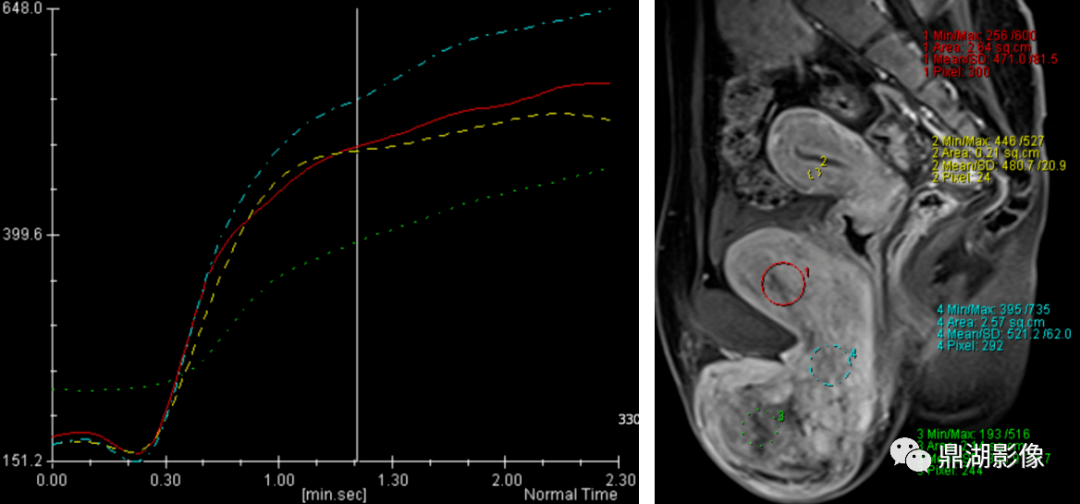

侵袭性血管黏液瘤影像诊断分析

图片尺寸1080x504